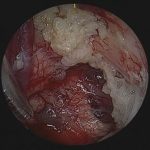

術中写真

No.’22_103 摘出 前

No.’22_103  摘出 中

No.’22_103 摘出 後